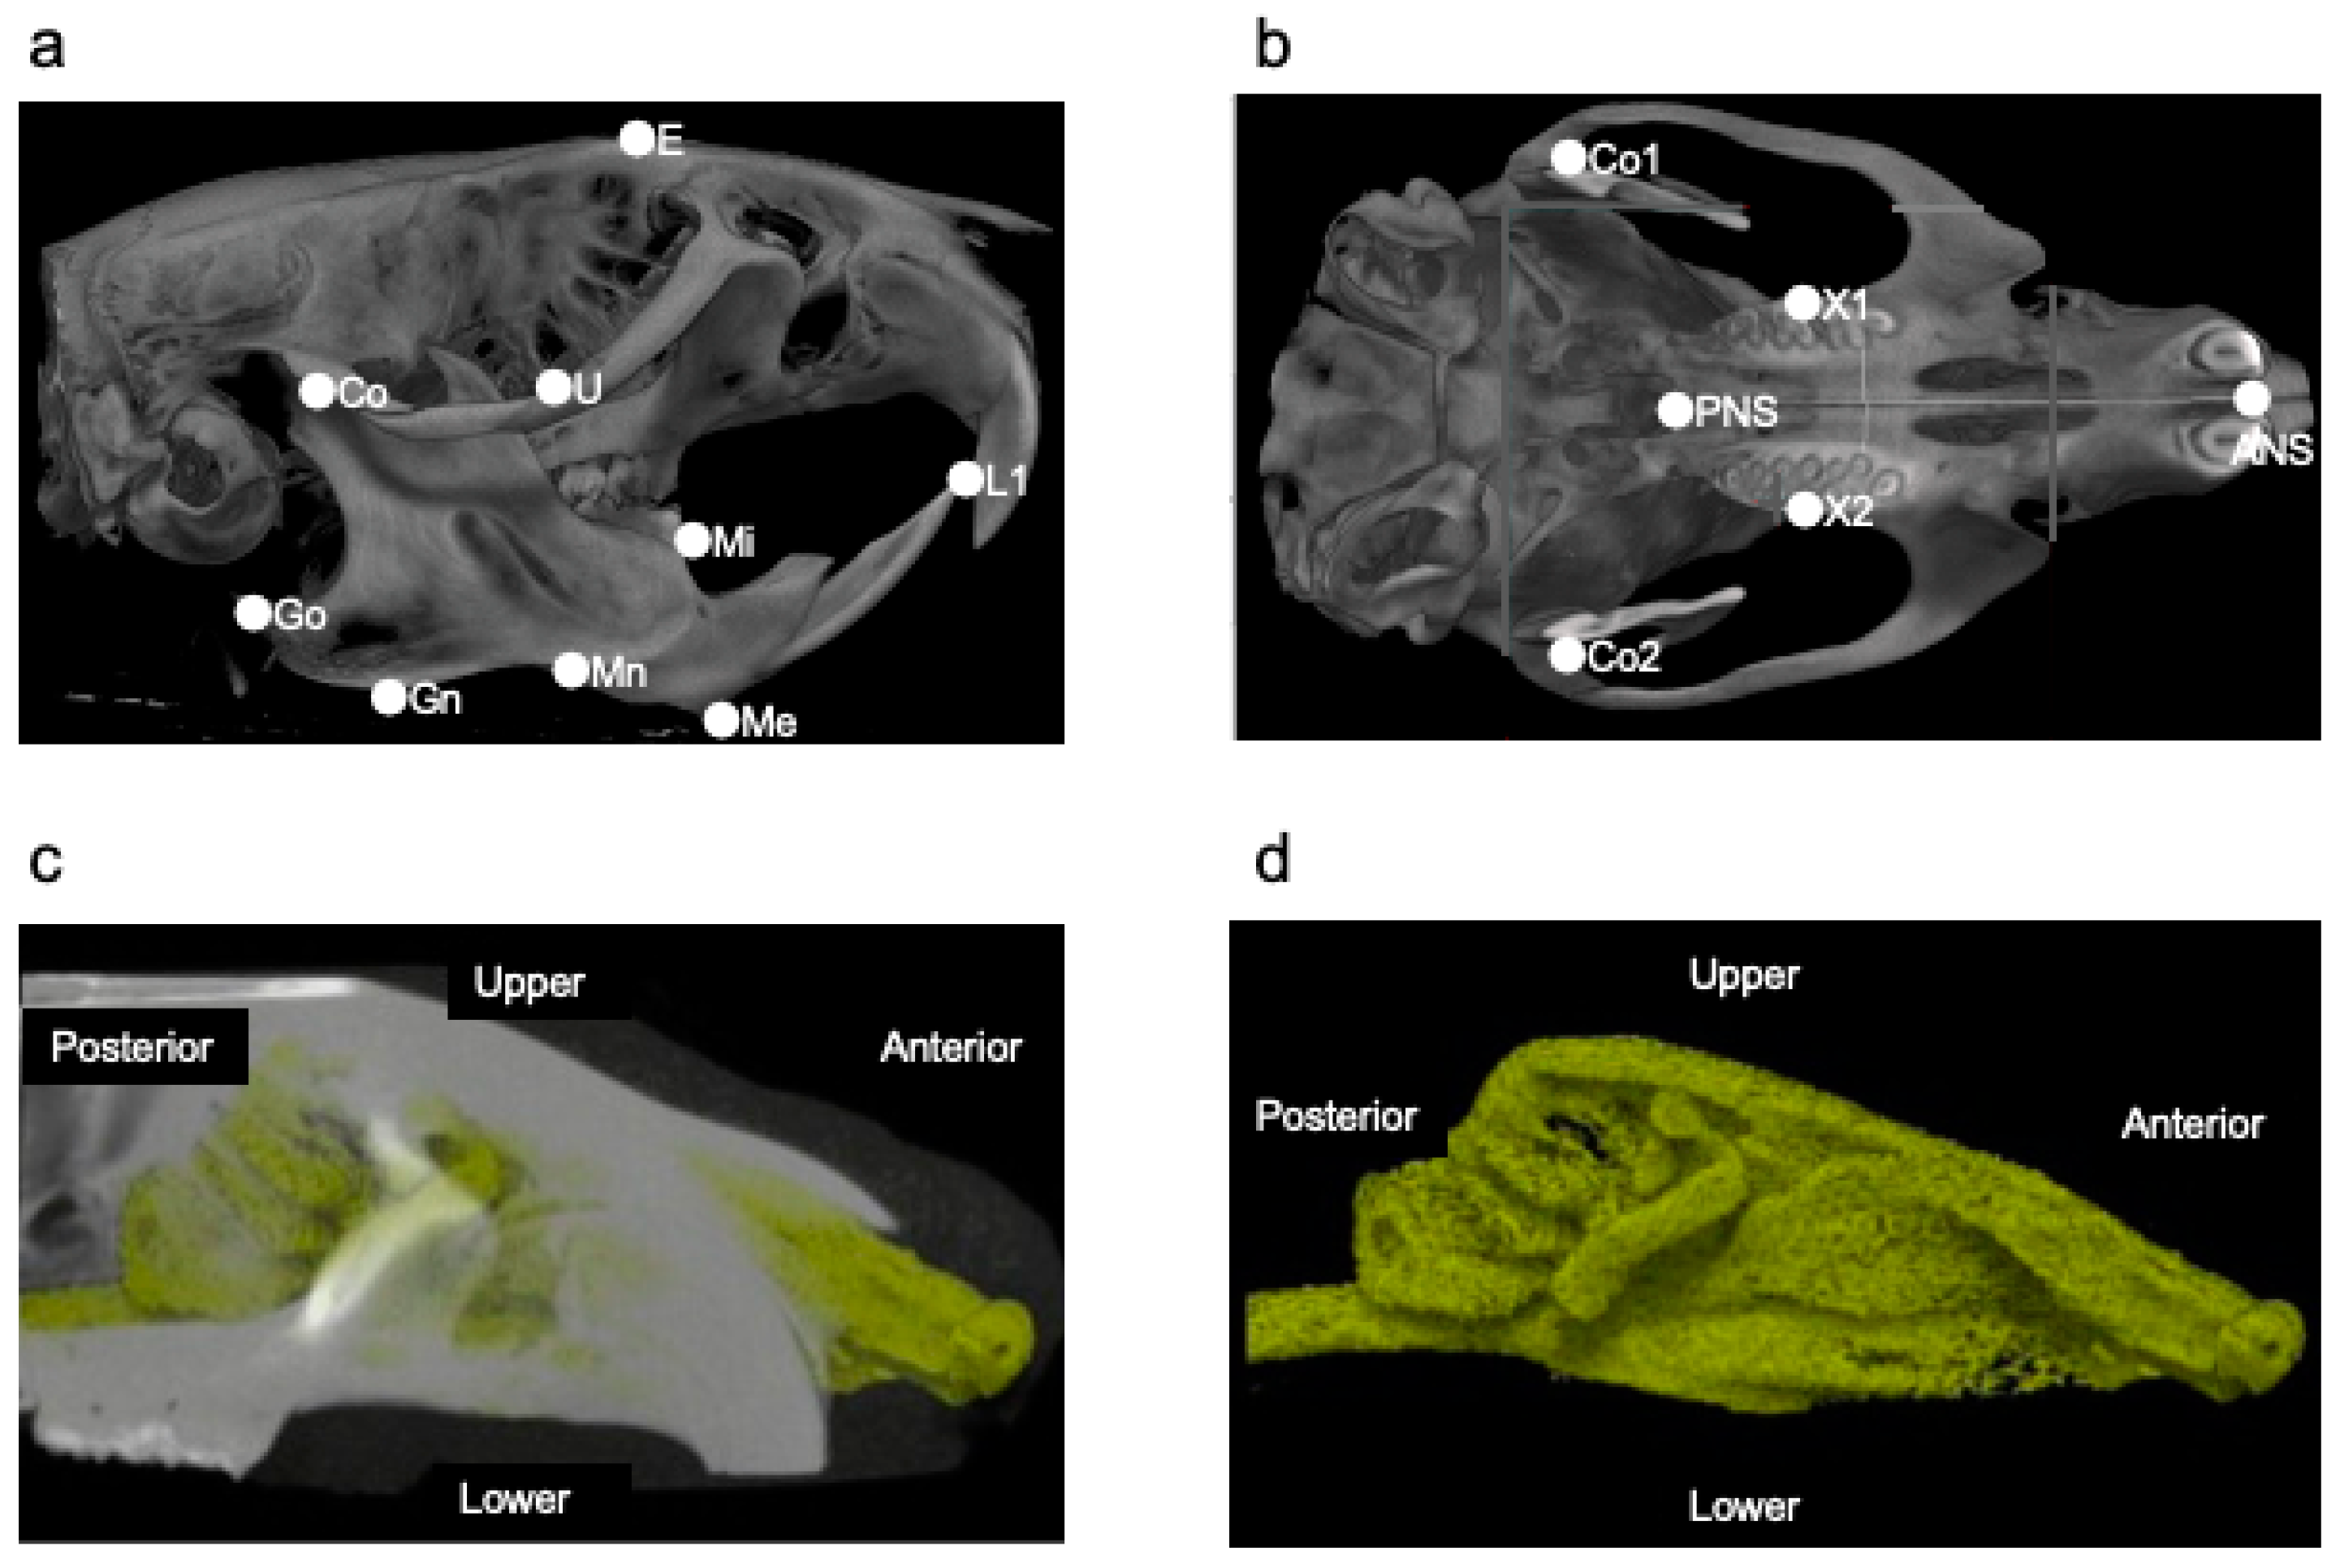

| Landmarks | Definition |

|---|---|

| E | The intersection between the frontal bone and the most superior and anterior point of the ethmoid |

| U | The intersection between the maxillary sinus and the distal surface of the third superior molar tooth |

| Co | The most posterior and superior point on the mandibular condyle (Co, right; Co2, left) |

| Go | The most posterior point on the mandibular ramus |

| Mn | The most concave portion of the concavity on the inferior border of the mandibular corpus |

| Gn | The most inferior point on the ramus that lies on a perpendicular bisector of the line Go–Mn |

| Me | The most inferior and anterior point of the lower border of the mandible |

| L1 | The most anterior and superior point on the alveolar bone of the mandibular incisor |

| Mi | The junction of the alveolar bone and the mesial surface of the first mandibular molar |

| ANS | The most anterior part of the palate |

| PNS | The most posterior part of the palate |

| X1 | The most anterior and superior point in the molar process of the right maxilla |

| X2 | The most anterior and superior point in the molar process of the left maxilla |

| Measurements | Interpretation |

| X1–X2 | Maxillary width |

| ANS–PNS | Maxillary length |

| U–E | Maxillary height |

| Co–L1 | Total mandibular length |

| Mi–L1 | Anterior mandibular length |

| Go–Mn | Posterior mandibular length |

| Co–Gn | Ramus height |

| Co–Me | Mandibular body length |

| Co1–Co2 | Mandibular width |